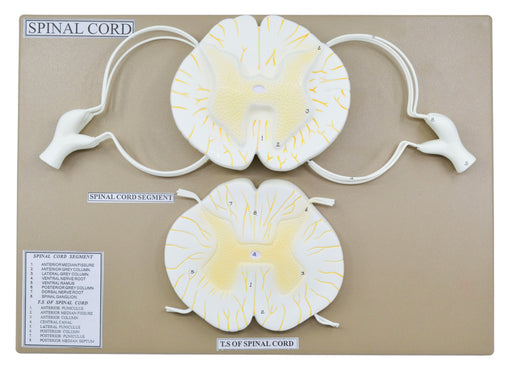

Spinal Cord Model, 17 Inch - Mounted - 10x Enlarged - Includes Nerve Branches - With English Key Card - Eisco Labs

LIFELIKE DESIGN || 3-dimensional spinal cord teaching demonstration model with lifelike design built from a custom mold DURABLE || Made of polyvin...

View full detailsAM16056 -